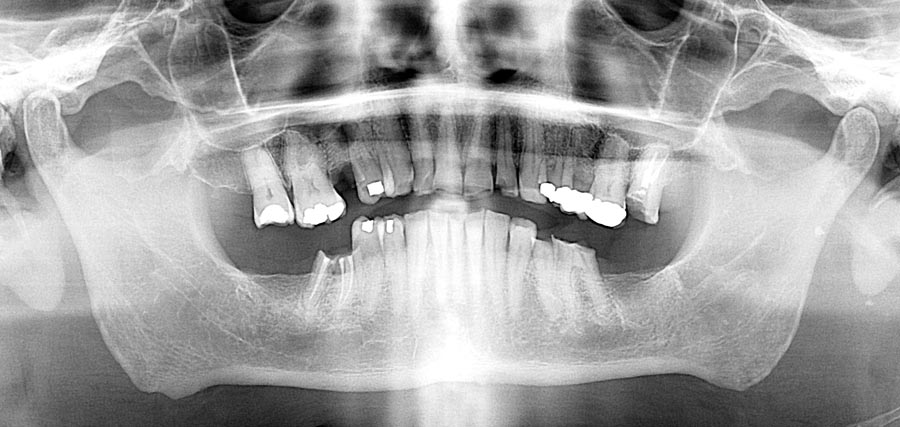

Pre-op, Panoramic x-ray. Note: Excellent bone. Possibility of saving teeth. Patient interested but reluctant.

Post-treatment panoramic image. This treatment is as good as humans can do in 2025. This patient was undecided whether to keep his teeth. We gave him the chance to consider this option but later he decided to have full mouth implants. We changed gears and were able to deliver World Class outcomes. We continue to encourage better homecare. This patient is from out of state so we haven’t seen his tissues in almost a year.